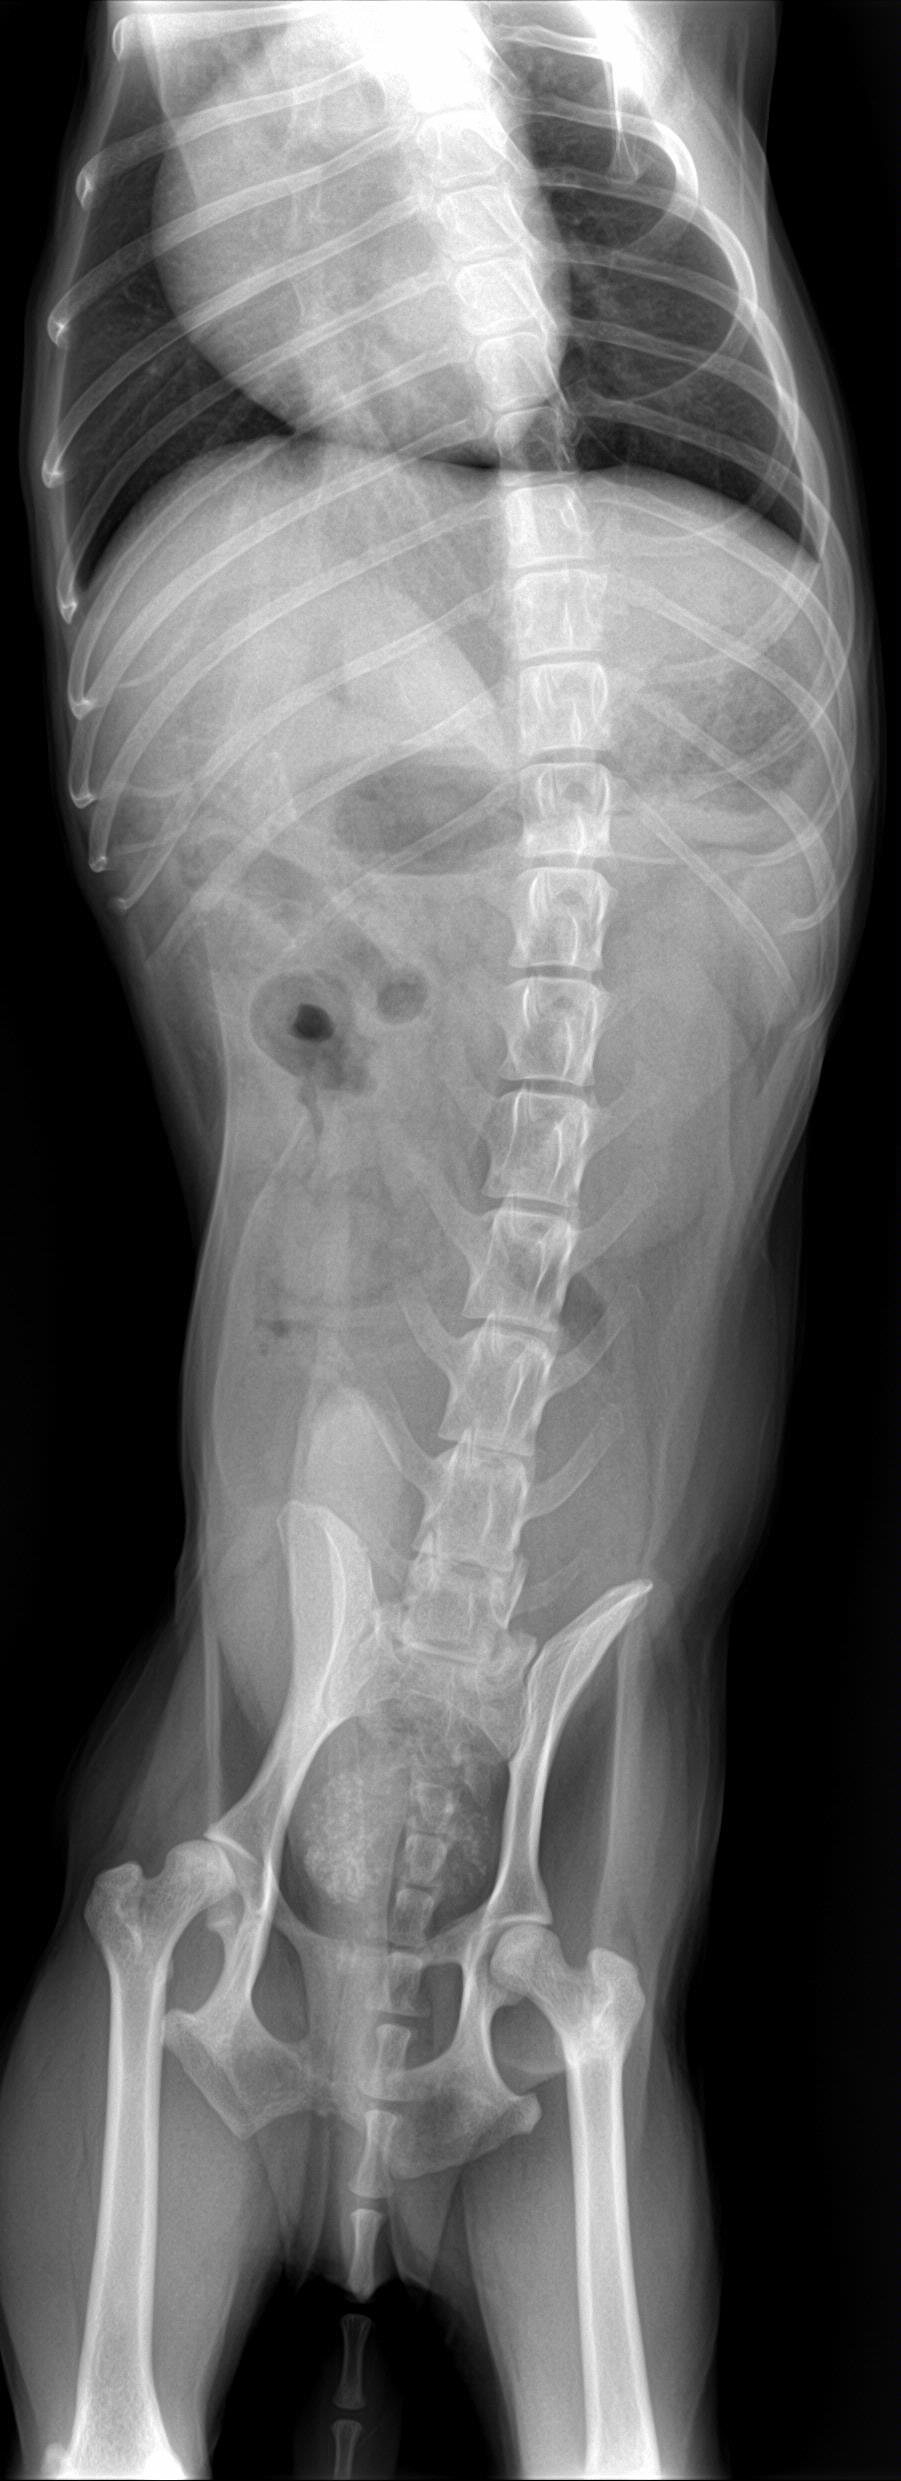

A 14-year-old neutered male Pomeranian dog was presented for evaluation of pollakiuria, diarrhea, inappetence, and lethargy. Abnormalities on physical examination included a painful, enlarged and symmetrical prostate, a very large and firm urinary bladder that could be expressed, and a grade III/VI heart murmur. On survey thoracic radiographs, calcification of the prostate gland was evident.